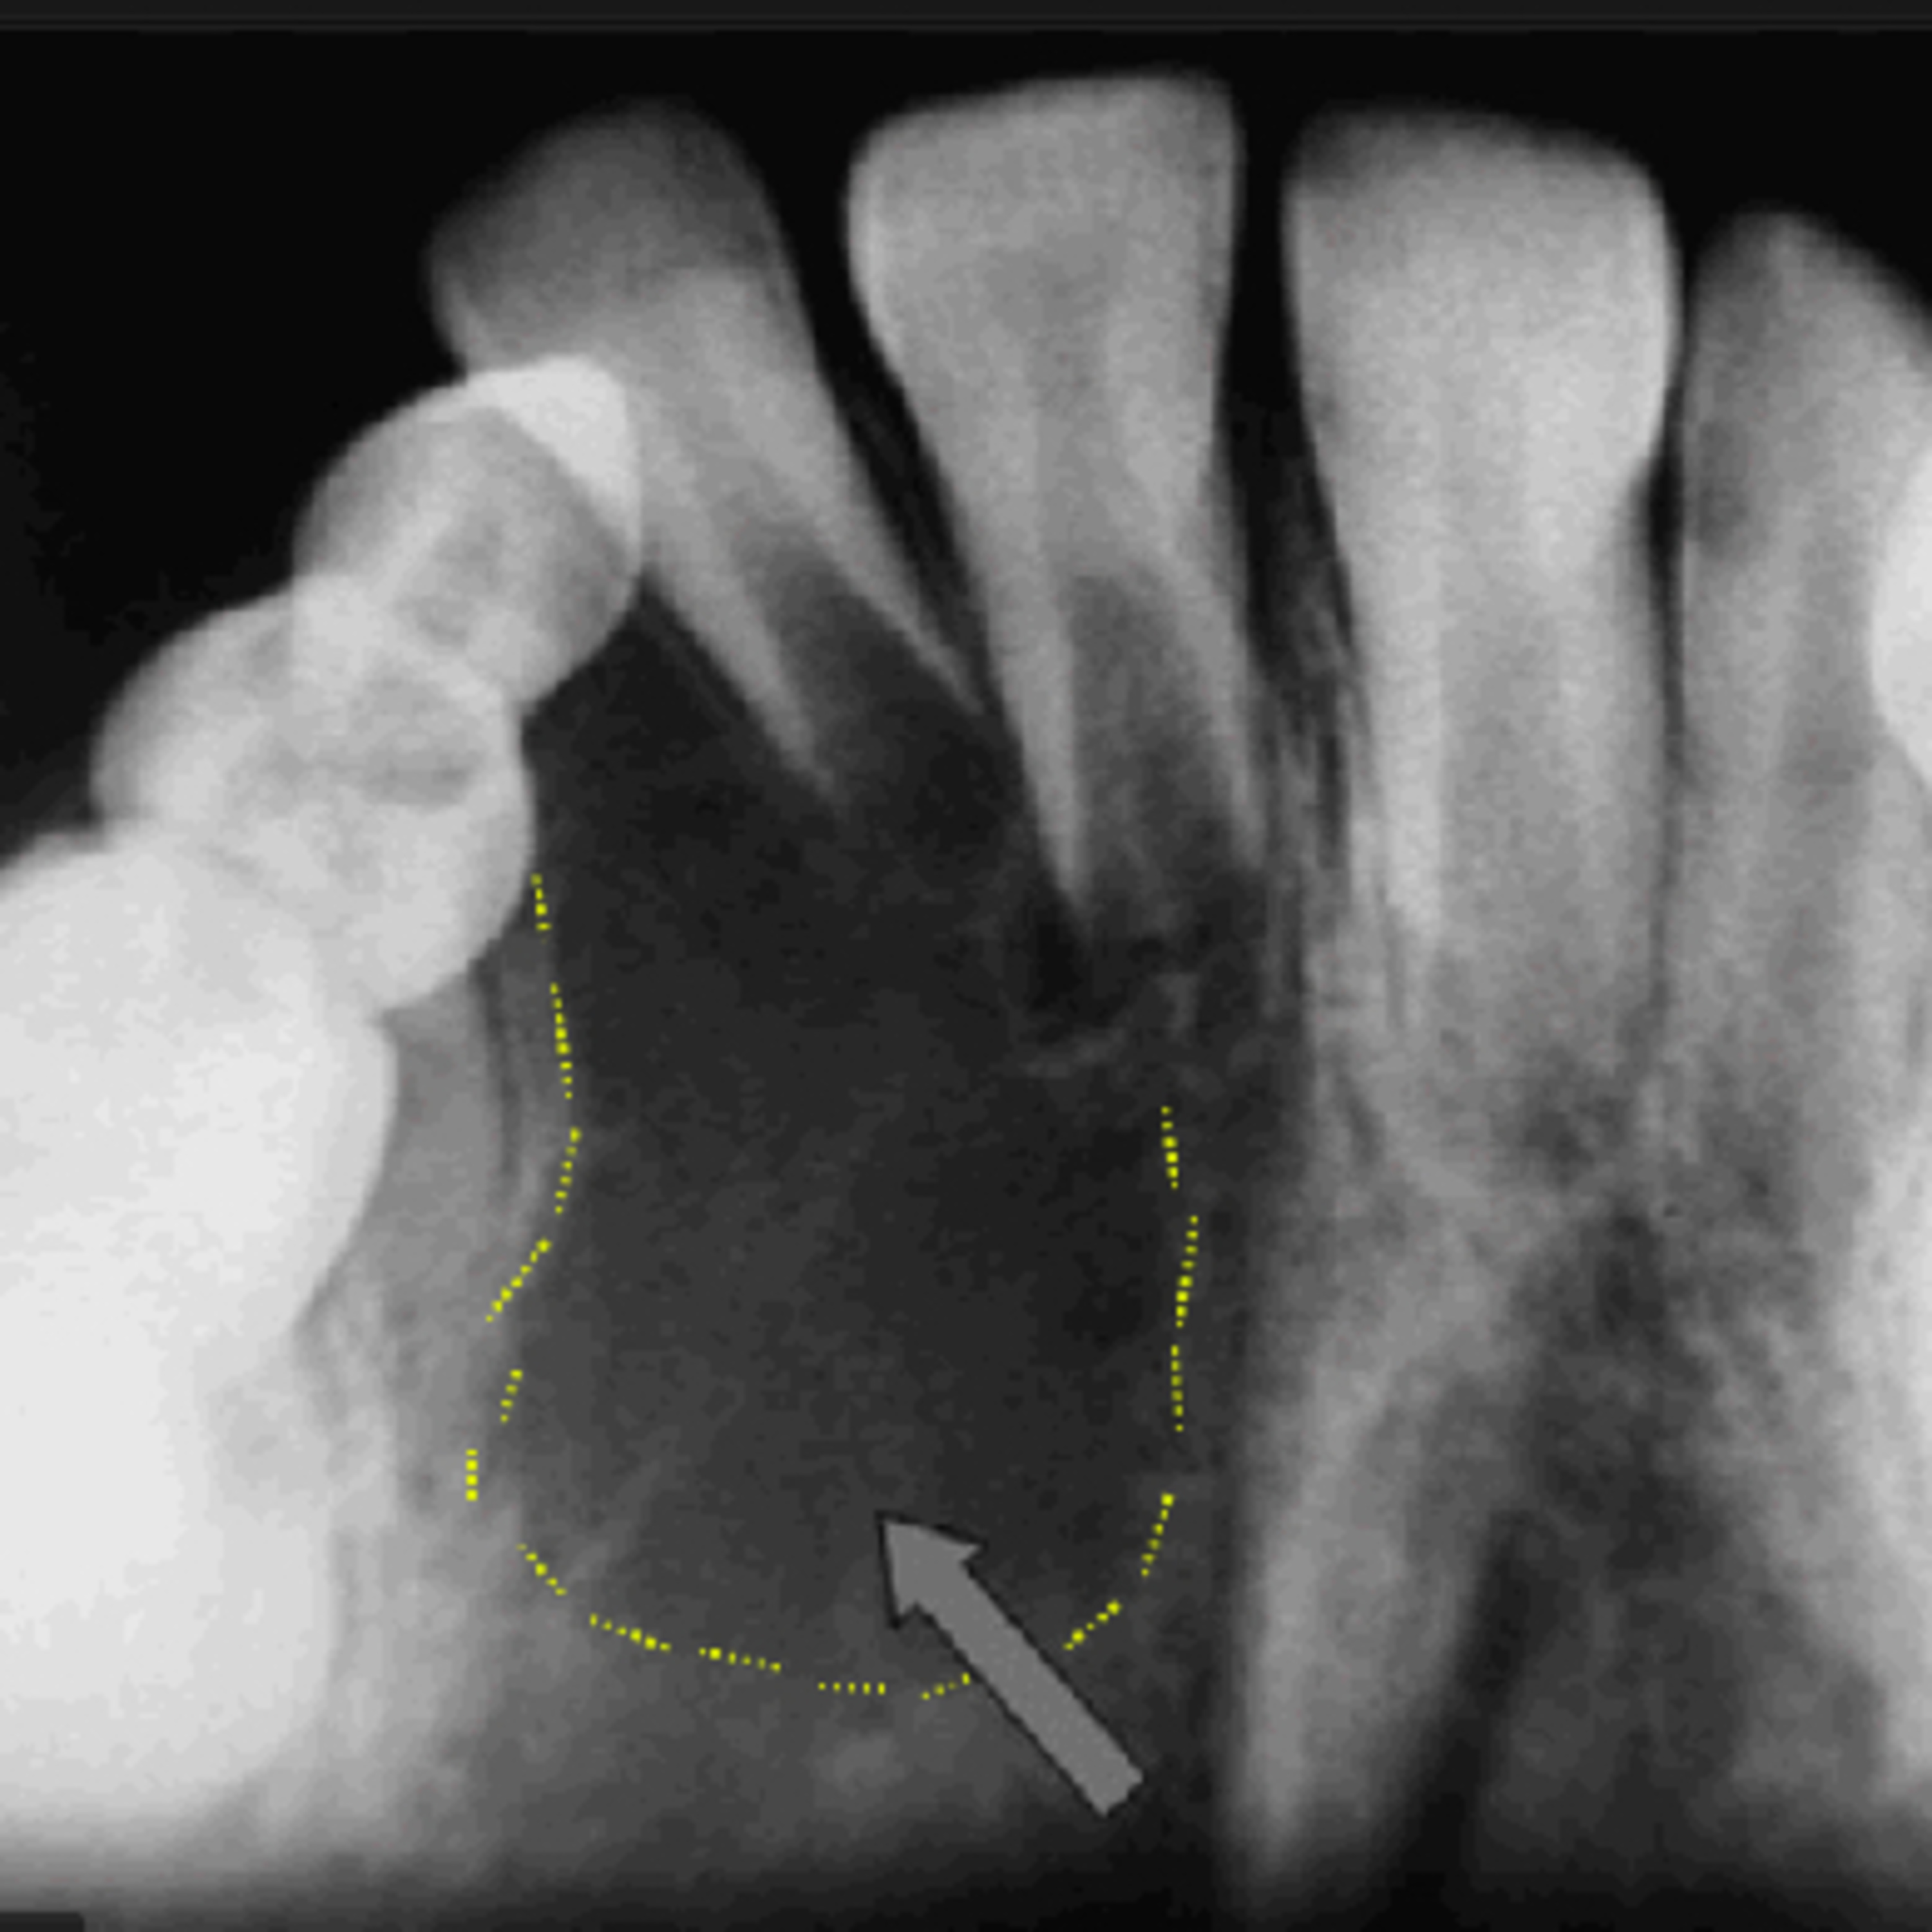

• Radiographic Findings:

- Exhibits a "soap bubble" or "honeycomb" appearance, radiolucent.

- Expansile, multilocular lesion with well-defined borders.

- Can cause thinning of the cortex, showing ballooning of the bone.